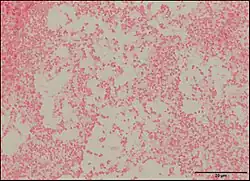

Pseudescherichia vulneris is a Gram-negative bacterial species. P. vulneris is a fermentative, oxidase-negative, motile rod, which holds characteristics of the family Enterobacteraceae. This bacterium can colonize in the respiratory tract, genital tract, stool, and urinary tract. However, P. vulneris is most often associated with wounds and has been known to colonize open wounds of both humans and animals. This association gave the bacterium its species name, vulneris, which is Latin for wound. It has also been infrequently reported in cases of meningitis. It was identified as Escherichia vulneris in 1982 with a 2017 genomic analysis of its original genus resulting in the creation of its new genus Pseudescherichia.[1][2]

P. vulneris has a rod-like (bacilli) shape, and it achieves motility using peritrichous flagella (covering the whole body of the bacteria). P. vulneris is facultatively anaerobic, and is not spore-forming. Optimal growth occurs at 35-37 °C, and it can colonize on a simple nutrient medium. Colonies are generally smooth and low convex with shiny surfaces.[3]